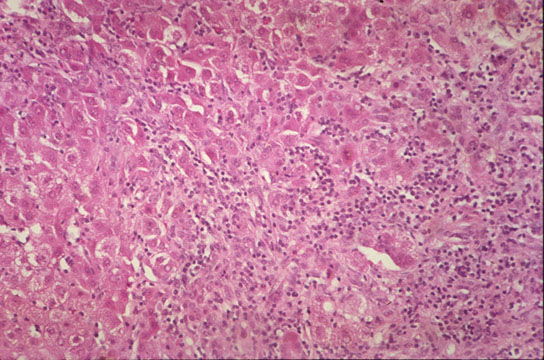

Kupffer cell hyperplasia

Fig 54 - KUPFFER CELL HYPERPLASIA: With cells full of lipofuscin an bile, result of phagocytosis of disrupted hepatocytes. Nodules of these cells may persist after healing (late nodules of Spatknoetchen).